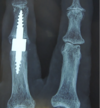

For metacarpophalangeal joints (at the base of the finger) and proximal interphalangeal joints (in the middle of the finger), prosthetic arthroplasties are preferred. These small prostheses provide good pain relief and can improve function in certain cases, depending on the severity of the preoperative damage and the healing quality of each patient.

Arthrodesis

For distal interphalangeal joints (at the tip of the finger, near the nail), arthrodesis is preferred, as it stabilizes the joint permanently, relieves pain and improves the aesthetics of the hand. Function may be temporarily impaired, but this segmental stiffness more than compensates for the functional impairment caused by the pain of osteoarthritis.